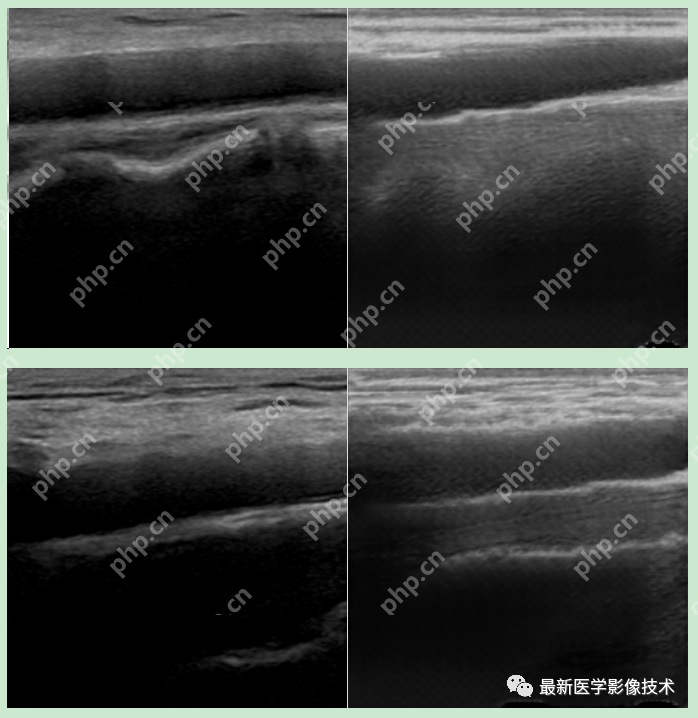

5、验证集部分生成结果

左图为低质量图像,中间为生成的高质量图像,右图为真实的高质量图像。